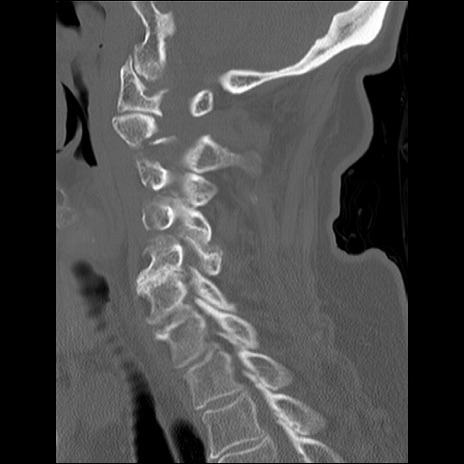

症例48 頚椎CT(矢状断像)

頚椎CT